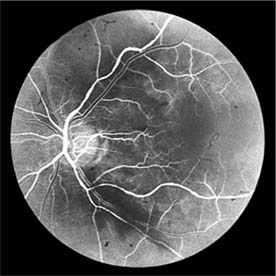

Figure 15-10

Figure 15-10: Accelerated hypertension. Fluorescein angiogram in a young man showing arteriolar constriction, dilation of capillaries with microaneurysms, and areas of closure. Marked disk edema is present.

Fluorescein angiography has made possible accurate documentation of these microcirculatory changes. In young patients with hypertension, arteriolar attenuation and occlusion are seen, and capillary nonperfusion can be verified in relation to a cotton-wool spot, which is surrounded by abnormal dilated capillaries and microaneurysms with increased permeability on fluorescein angiography.